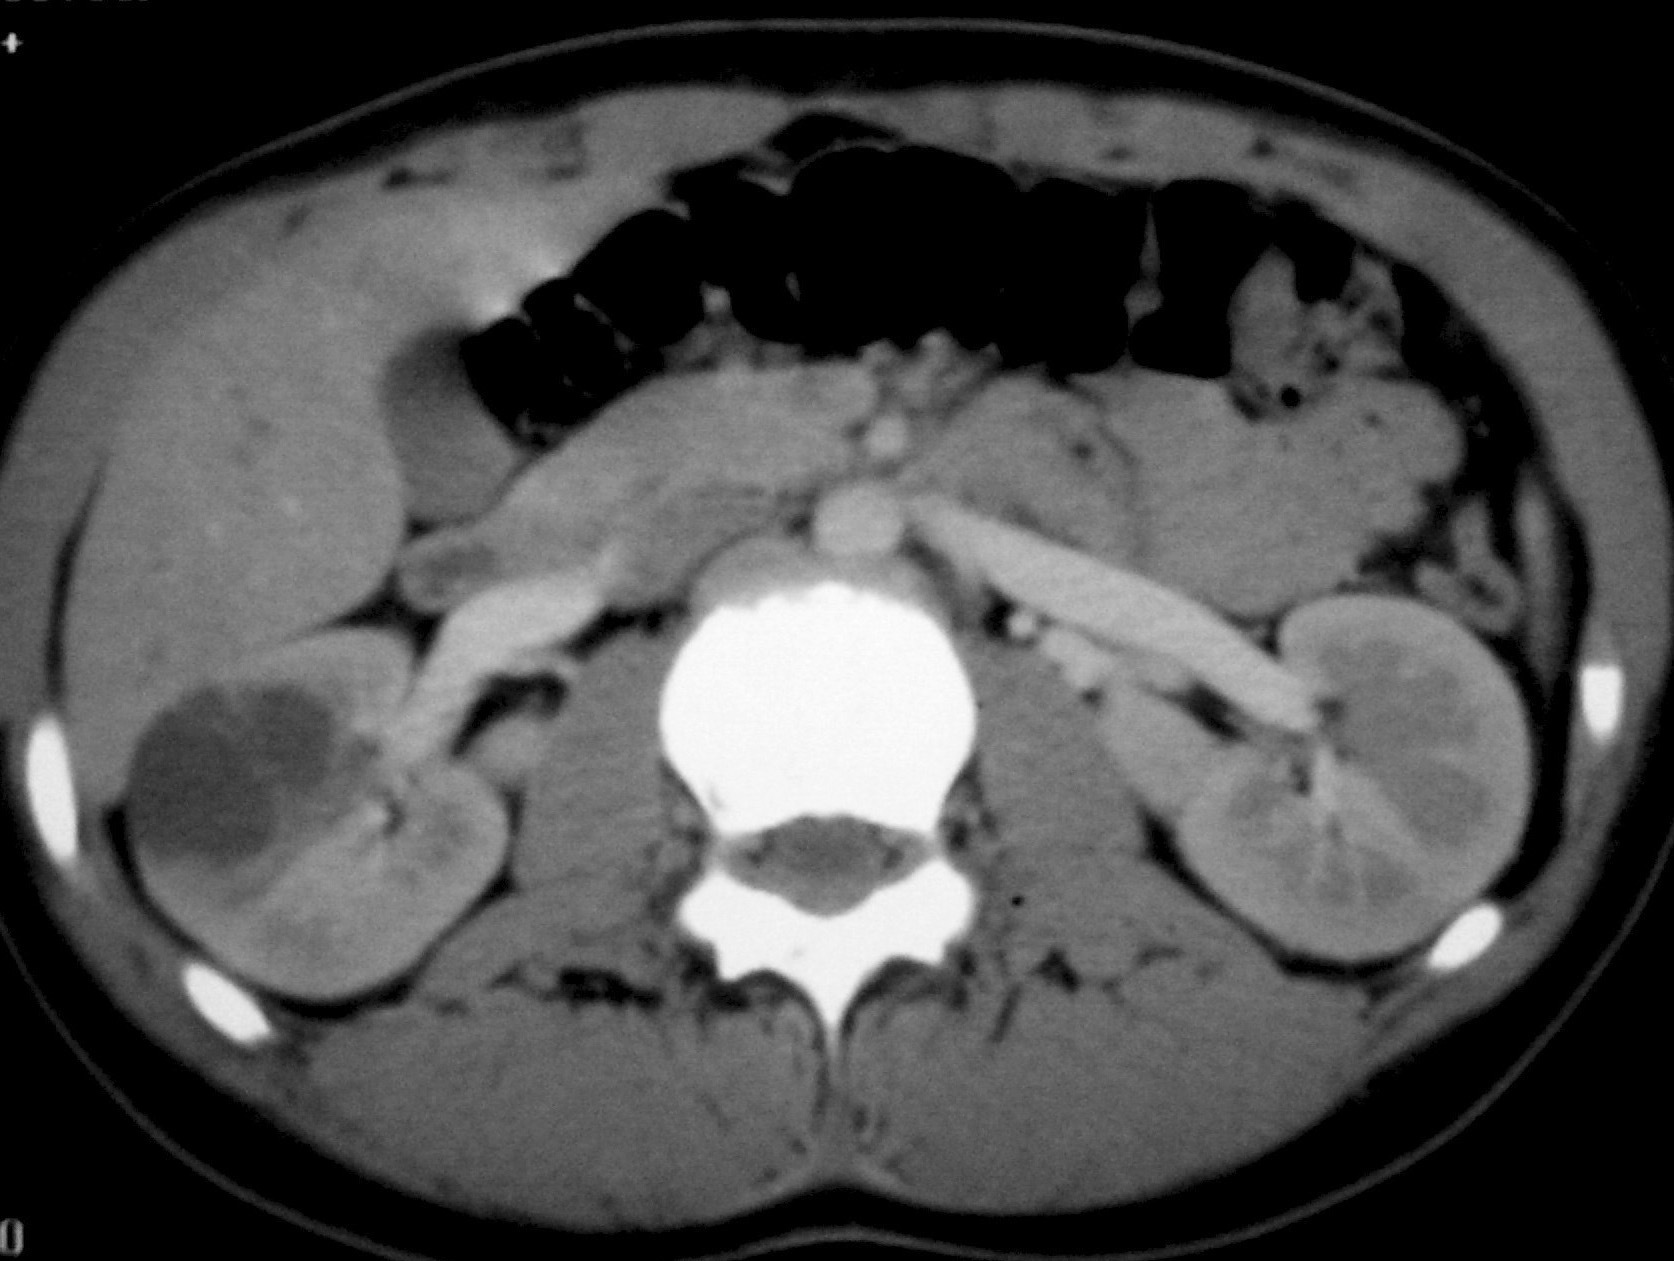

La única paciente con angiomiolipoma renal fue una niña de 10 años con esclerosis tuberosa. En el riñón derecho se identificó una tumoración en el polo superior, con gran crecimiento extrarrenal, densidad homogénea, mayor que la del parénquima renal y menor que la del hígado y relativamente ecogénica (fig. 9). No se constataron áreas grasas, tratándose de un angiomiolipoma con poco componente graso. En el riñón izquierdo se identificaron dos lesiones de pequeño tamaño con atenuación grasa compatibles con angiomiolipomas. Como hallazgos asociados se observaron en el hígado múltiples lesiones con contenido graso de características similares, compatibles con angiomiolipomas intrahepáticos.

Fig. 9. Angiomiolipoma. Niña con esclerosis tuberosa. (A) Ecografía abdominal. Corte renal derecho. Masa renal de ecogenicidad heterogénea y contornos lobulados. (B) Tomografía computarizada abdominal. Masa (M) en riñón derecho. No se identifica componente graso. En el hígado existen tres lesiones de atenuación grasa correspondientes a angiomiolipomas hepáticos (1, 2, 3).